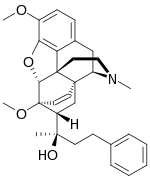

Several semi-synthetic opioids were developed in Germany in the 1910s. The first, oxymorphone, was synthesized from thebaine, an opioid alkaloid in opium poppies, in 1914.[228] Next, Martin Freund and Edmund Speyer developed oxycodone, also from thebaine, at the University of Frankfurt in 1916.[229] In 1920, hydrocodone was prepared by Carl Mannich and Helene Löwenheim, deriving it from codeine. In 1924, hydromorphone was synthesized by adding hydrogen to morphine. Etorphine was synthesized in 1960, from the oripavine in opium poppy straw. Buprenorphine was discovered in 1972.[228]

The first fully synthetic opioid was meperidine (later demerol), found serendipitously by German chemist Otto Eisleb (or Eislib) at IG Farben in 1932.[228] Meperidine was the first opiate to have a structure unrelated to morphine, but with opiate-like properties.[199] Its analgesic effects were discovered by Otto Schaumann in 1939.[228] Gustav Ehrhart and Max Bockmühl, also at IG Farben, built on the work of Eisleb and Schaumann. They developed "Hoechst 10820" (later methadone) around 1937.[230] In 1959 the Belgian physician Paul Janssen developed fentanyl, a synthetic drug with 30 to 50 times the potency of heroin.[211][231] Nearly 150 synthetic opioids are now known.[228]

Opium alkaloids and derivatives

Phenanthrenes naturally occurring in (opium):